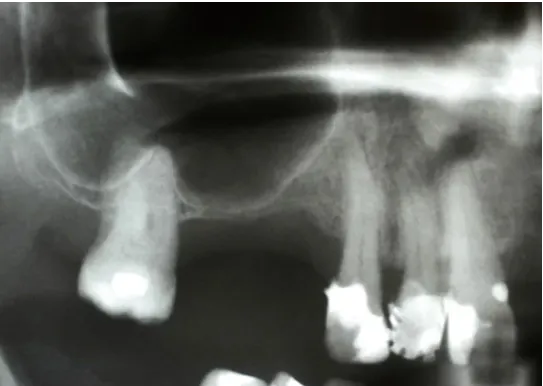

Odbudowa kostna w ODCINKACH BOCZNYCH SZCZĘK - PODNIESIENIE DNA ZATOKI SZCZĘKOWEJ (SINUS LIFT)

Technika odbudowy kostnej stosowana w celu wszczepienia implantów w zanikłe, boczne odcinki szczęk. Najistotniejszą przyczyną utraty kości wyrostka zębodołowego szczęk w odcinkach bocznych są ekstrakcje zębów. Niedostatek kości w wymiarze pionowym stanowi szczególną anatomiczną przeszkodę dla implantacji w okolicy dna zatoki szczękowej. Chcąc odbudować uzębienie i przywrócić funkcję żucia, trzeba podjąć wieloetapowe leczenie rekonstrukcyjne.

Zabiegiem, który rozwiązuje ten problem, jestpodniesienie dna zatoki szczękowej (sinus lift), czyli odbudowa kostna w okolicy zębów trzonowych. Ubytek kości uzupełniany jest materiałem kościotwórczym, który układany jest pod błoną wyścielającą zatokę szczękową, zwaną membraną Schneidera. Zmniejszając objętość zatoki szczękowej, tworzy się tym samym stabilną strukturę kostną, umożliwiającą zabieg implantacji wszczepów śródkostnych.

Metody operacyjnego podniesienia zatoki szczękowej